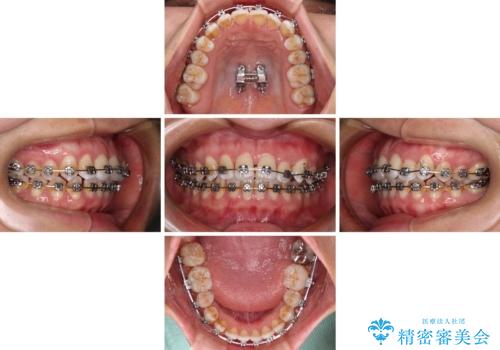

前歯の反対咬合 急速拡大装置とワイヤー装置であっという間の矯正治療

- 全顎的なクロスバイトと反対咬合を気にして来院された患者様です。

骨格的に下顎が前方位にありましたが、歯並びにより下顎が本来の位置よりも前方位に誘導される咬み合わせとなっていました。

上顎歯列および上顎骨が下顎に対して狭小であることが原因であるため、上顎の急速拡大装置を使用して上顎骨を側方に拡大することで反対咬合を改善し、ワイヤー装置で歯列を整えることとしました。

上顎の拡大に伴い反対咬合があっという間に改善されました。

元々の歯列不整は軽微であったため、僅か1年の期間で治療を終えることができました。